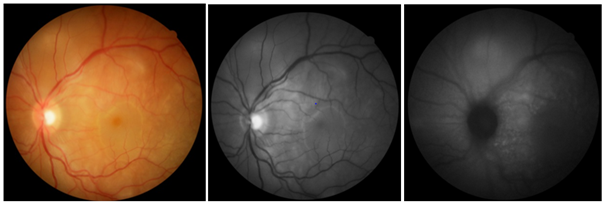

Laboratory tests showed the following results: complete blood count without changes, serology for non-reactive HIV, VDRL 1/128, toxoplasmosis IgG positive (185.0) and IgM negative (0.43), serologies for hepatitis B and C negative, FAN negative and negative rheumatoid factor. Ultrasonography was then performed in both eyes, which showed the presence of multiple pockets of serous retinal detachment with a macula glued to the right eye; and multiple pockets of serous retinal detachment, with macular edema in the left eye. With the diagnosis of Vogt-Koyanagi-Harada syndrome closed, treatment with oral prednisone 1 mg / kg was initiated, in addition to maintaining 1% prednisolone eye drops at weekly weaning. Two weeks after the beginning of oral immunosuppressive therapy, there was an improvement in visual acuity, which presented, with correction, in DO, 20/30 and in LEFT EYE, 20/40; in addition to reduction of retinal edema. Intraocular pressure using Goldmann's tonometry, OD 24mmHg and LEFT EYE 26mmHg, and associated brimonidine eye drops with timolol of 12 / 12h in both eyes (BE). In subsequent consultations, the patient presented negative VDRL after treatment for syphilis and control of intraocular pressure using hypotensive eye drops. Slow weaning from oral prednisone was carried out over the course of a year and maintained at 20 mg / day with stabilization of visual acuity at 20/20, with correction, in both eyes. One year after the onset of the condition, the patient presented to the retinography the presence of a "sunset" image in the right eye (Figure 3a) and in the left eye (Figure 3b)  Angiography showed the presence of hyperfluorescent lesions due to a window defect, due to the mobilization area and atrophy of the retinal pigment epithelium, seen during the examination, both in the left eye (Figure 5a) and in the right eye (Figure 5b). In an attempt to completely withdraw oral medication with slow weaning, visual loss of three lines was observed in the Snellen table in RIGHT EYE (20/40) and LEFT EYE remained stable at 20/20. Thus, a dose of 20 mg/ day of oral prednisone was maintained for two months, with slow weaning to 5 mg/ day, but again there was a worsening of VA (RIGHT EYE: 20/40 and LEFT EYE: 20/30). Thus, it was decided to suspend oral prednisone at 20mg / day and start injectable treatment with adalimumab. The patient is waiting for the medication to be released by the Unified Health System.

Figure 5 Fluorescein angiography.

Two months after the onset of the condition, dermatological changes may also appear, constituting the convalescent. They are poliosis, vitiligo and alopecia. However, the study patient did not present any evident dermatological symptoms. The characteristic ‘’ sunset ’’ eye fundus was described in the assessment made one year after the onset of the condition.15 The recurrent chronic phase may or may not occur. When present, recurrent retinal detachments, formation of retinal neovascular membranes, glaucoma and cataracts occur. These complications occur in about 1/3 of the patients.14,15 Our patient progressed well with treatment and did not show recurrence symptoms, despite the difficulty in weaning from therapy and staying on medication for more than a year. Regarding the most used complementary exams, in the OCT the most common findings are folds and serous detachment of the retinal pigment epithelium (RPE), presence of septa and areas of subretinal fluids, with macular area thickness varying between 700-900 microns ( 12.16). Ocular ultrasound can show choroidal thickening, papilla edema and areas of serous retinal detachment. Regarding fluorescein angiography, fluorescein pooling can be seen in areas of serous detachment and leakage of the optical disc.12 In the patient, the OCT (one year after the onset of the condition) showed an increase in foveal thickness and cysts in the internal retinal layers; on ultrasound, we see the presence of multiple pockets of serous retinal detachment; and in fluorescein angiography, we observed hyperfluorescent areas by window and pooling defect. Such findings corroborate the evidence in the literature cited above. Treatment must be early and it is done with the use of corticosteroids and immunomodulatory drugs to control the effects produced by autoimmunity and reduce damage.1 After the symptoms improve, the treatment should be discontinued slowly, from 3 to 6 months, and should be maintained for about a year in case of recurrences. In severe forms of the disease, there is benefit in the triple use of immunosuppressive therapy, which consists of prednisolone, azathioprine and cyclosporine, simultaneously.1 The inflammatory and exudative retinal process can improve with the application of intravitreal triamcinolone injection.17 Some studies suggest that sub-tenonian injection of triamcinolone should be an initial treatment for relapse of VKH in pregnant women.18 The study patient improved only with prolonged use of oral and topical corticosteroids, not requiring immunomodulatory therapy. Poor access to immunomodulatory medications through the Unified Health System also restricts treatment to corticosteroids. The main complications of VKH syndrome are secondary glaucoma, cataracts, choroidal neovascularization and subretinal neovascular membrane in the recurrent chronic phase.14,19 The study patient did not have any of these complications. Chronicity of the condition usually occurs when there is a delay in diagnosis, often due to ignorance of the initial clinical manifestations of the disease. The time between the onset of symptoms and the institution of immunosuppressive therapy is essential for final visual acuity, influencing the prognosis of the disease.